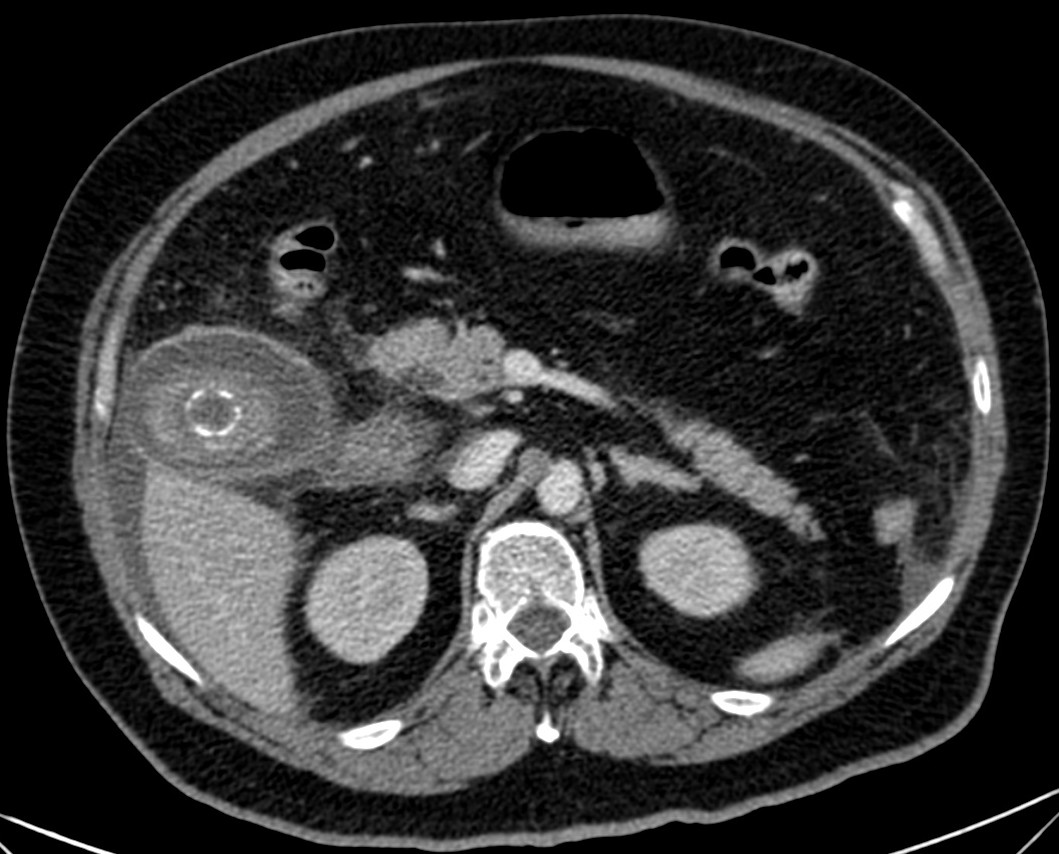

Se realizó posteriormente TC abdominal por mala evolución del paciente:

– La TC se reserva para pacientes con dudas diagnósticas o con discrepancia clínico ecográfica. Se obervarán los mismos hallazgos que en la ecografía, además del aumento de densidad de la pared de la vesícula, del parénquima hepático o especialmente la presencia de otras complicaciones.